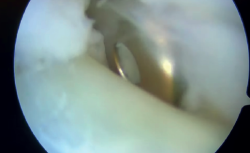

Un año y medio después de la lesión inicial, se realizó una segunda cirugía artroscópica de tobillo. El procedimiento reveló sinovitis anterior de la articulación tibiotalar, que fue desbridada con un sinoviotomo. El CFL estaba intacto, mientras que se observó una rotura parcial menor del ATFL, que se consideró clínicamente sin relevancia. En segundo lugar, se realizó una tenoscopia de la vaina de los tendones peroneos, revelando una rotura de la vaina y el tendón peroneus brevis con integridad del retináculo, visualizándose la fijación proximal del injerto en la fíbula que estaba en contacto con el tendón peroneus brevis, el cual estaba parcialmente desgarrado (Figura 3).

Figura 3. Tenoscopia de la vaina peronea en el tobillo derecho, donde se observa el dispositivo de fijación proximal dentro de ella, contactando con el tendón del peroneo corto durante las maniobras dinámicas.